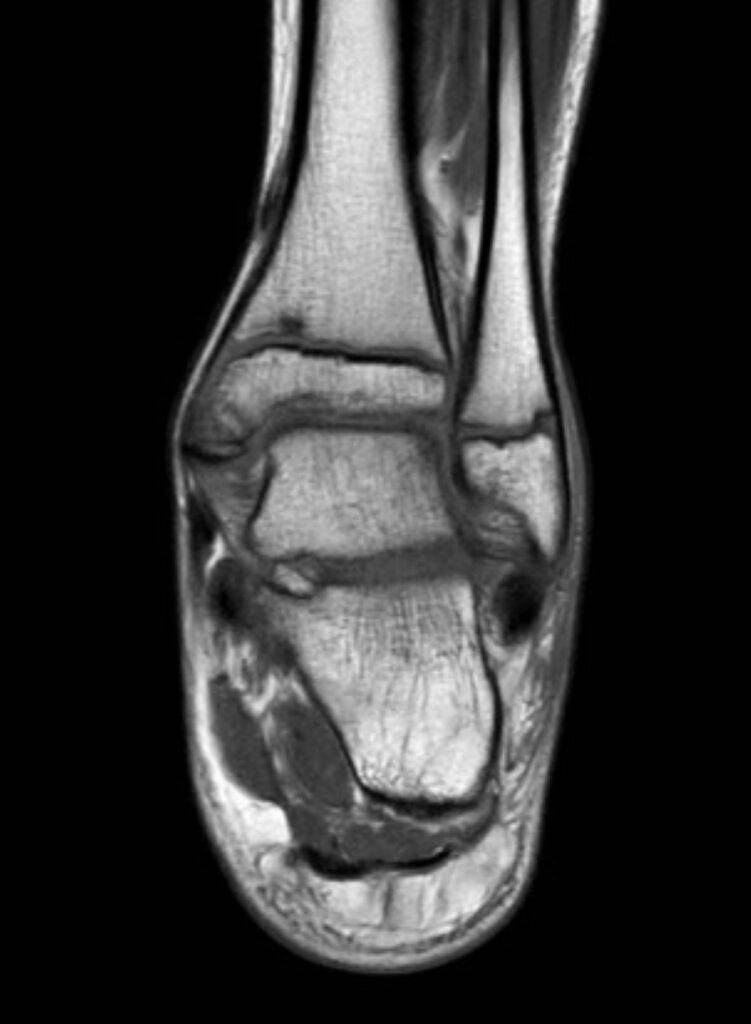

Je nach medizinischer Fragestellung wird eine spezifische Körperregion gescannt. Der Körper kann eingeteilt werden in Kopf und Hals, Thorax (Brust, Lunge, Herz), Abdomen und Becken (Bauchraum, Leber, Niere, Blase u.w.), Rücken (Wirbelsäule) und Extremitäten (Arme, Schulter, Beine, Füße).

Muskeln und GelenkeViele große Gelenke im Körper sind vielfältig, da diese aus Sehnen, Bändern, Gelenken und Muskeln bestehen. Diese lassen sich durch die MRT besonders gut betrachten, wie z.B. das Kniegelenk.

2. Verletzungen: oft kommt es zu Schulunfällen, dabei kann es zu Verletzungen in allen Körperbereichen kommen, je nach Verletzung kann zur genauen Diagnose eine MRT bei Kindern oder Jugendlichen notwendig sein

3. Erkrankungen des Bewegungsapparats: klagt Ihr Kind über Gelenk- oder Rückenschmerzen, Muskelschwäche oder ähnlichen Beschwerden, kann die MRT-Untersuchung helfen, die entsprechende Ursache zu finden